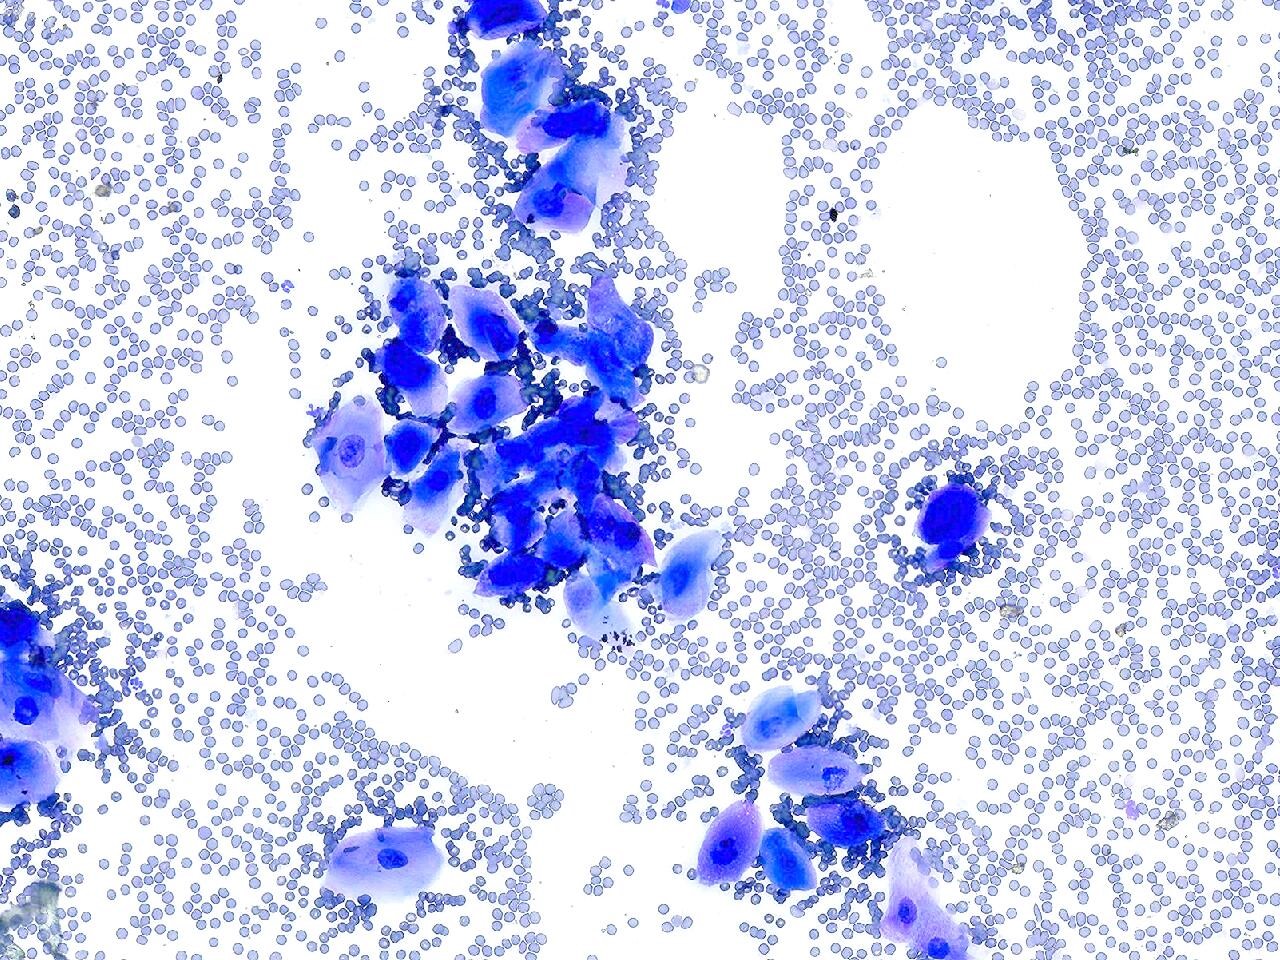

Young hound with a mass on the lip

A fine-needle biopsy of the mass is obtained. Cytology of the mass returns and is shown.